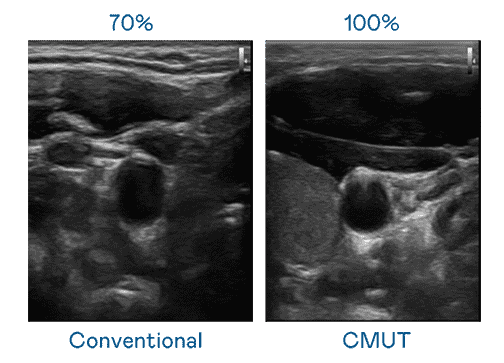

CMUT 技术是一种用电容式微机电元件来产生超音波讯号的技术。。。。与传统 PZT 压电式技术相比,,CMUT 频宽增加 30%,,,更宽频的超音波讯号让影像解析度大幅提升,,是实现高影像品质医疗超音波扫描、、促进精准医疗发展的关键技术。。

大频宽带来超清晰影像

超音波影像的解析度高低,,,首先取决于探头能发出的讯号频宽。。。。口袋牛店 CMUT 可提供高清晰的超音波讯号,,,提供高频宽、、高灵敏度、、、影像纹理细节更高的超音波影像,,协助医护人员缩短影像判读时间及利用精准的医疗影像进行诊断。。